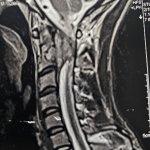

جراح مغز و اعصاب و ستون فقرات.دیسک کمر و دیسک گردن .عصب سیاتیک.درمان شکستگی مهره ها و جراحی تومورهای مغز و نخاع.درمان کمر درد و درد گردن مزمن لیزر دیسک کمر بدون نیاز به جراحی باز..تزریق داخل کمر.تزریق اینترا فورامینال و اعمال کم تهاجمی ستون فقرات.

گالری